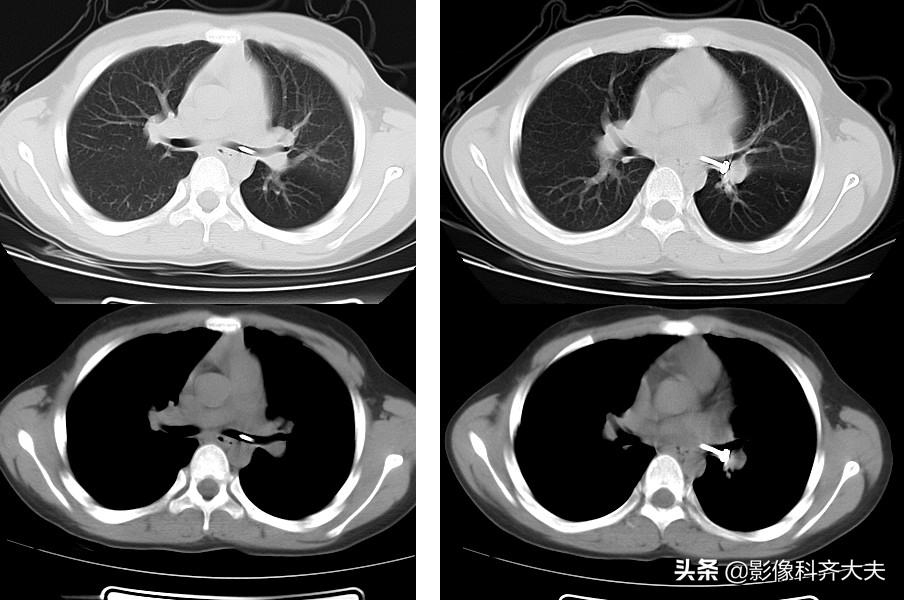

轴位图

轴位显示左肺明显肺气肿,左侧支气管似有异常。为进一步明确诊断,遂进行CT三维重建

进行MPR(多平面重组)冠状位重建,清晰显示左侧左侧支气管有异物。

最小密度投影重建对于异物的显示更加清晰,红色箭头所示。

病例6、病史:女,两岁,吃花生时喝水引起呛咳。

轴位显示左侧支气管疑似异物,红色箭头。

冠状位重建清晰显示左侧支气管异物,红色箭头所示。

最小密度投影显示的更加清楚。